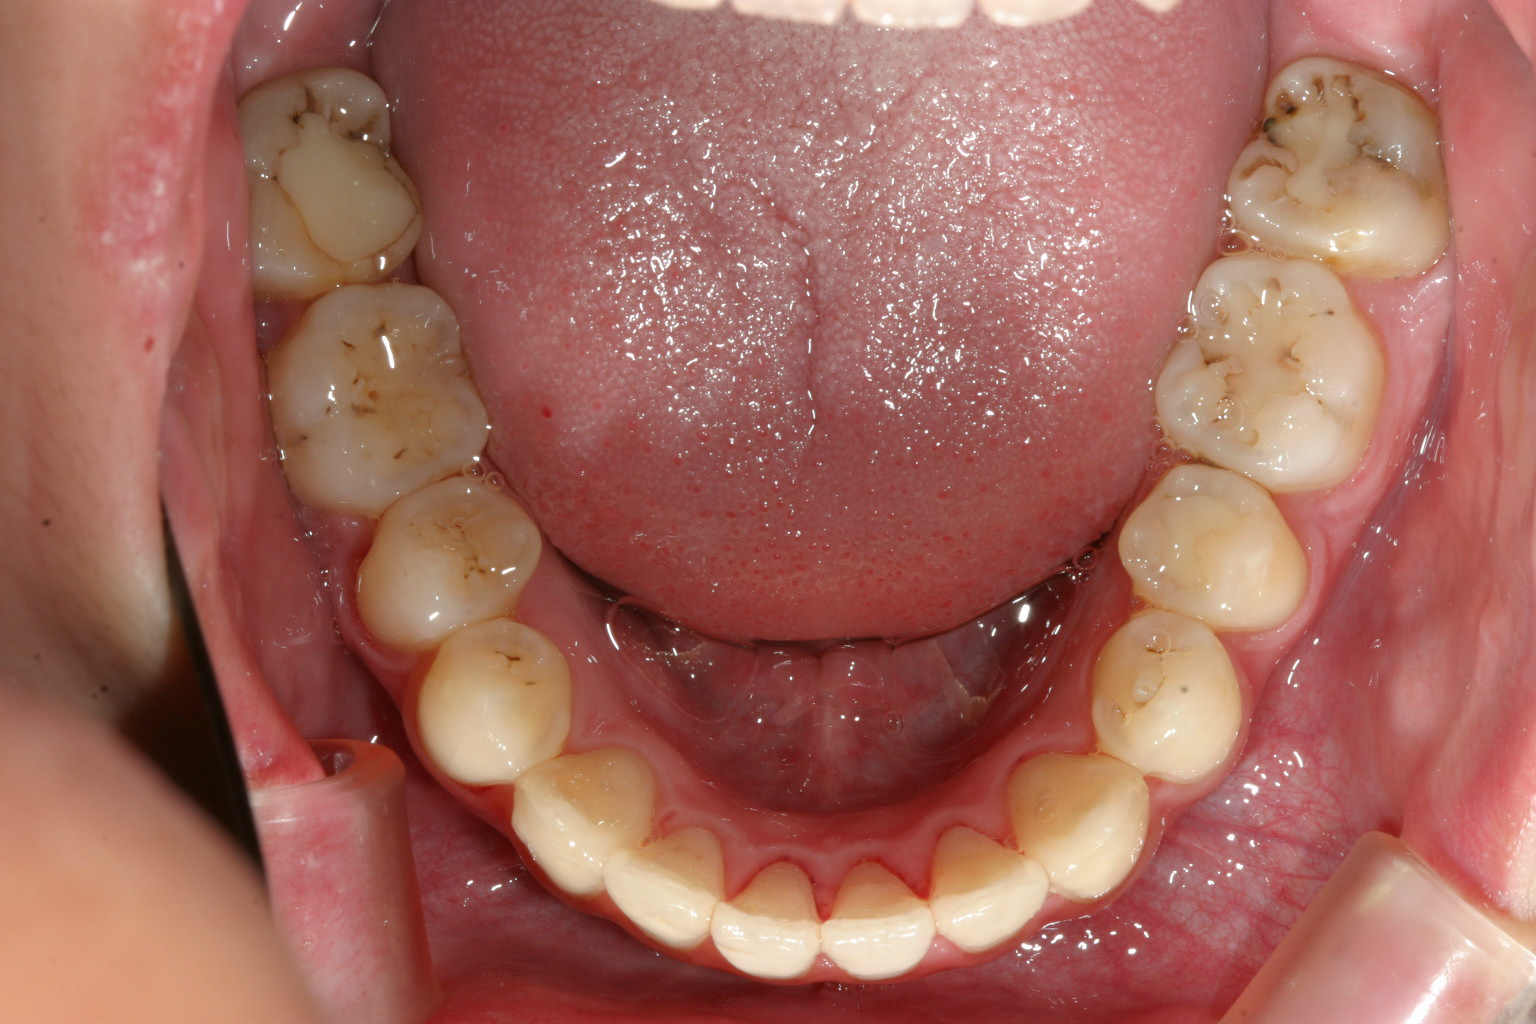

両サイドの小臼歯抜歯して前歯の出っ張りを中に入れました。

下顎は非抜歯です。アーチをU字に変えて綺麗に並んでます。

上下の出具合も抜群です。 加速矯正装置使用ですから期間も短縮されました。